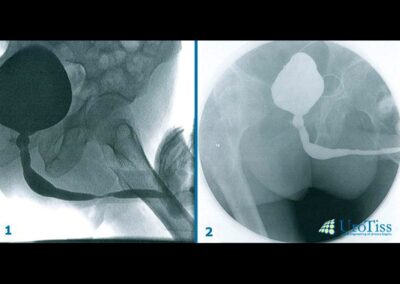

Eine Harnröhrenstriktur wird zuerst radiologisch dargestellt, um den Grad der Enge und deren Länge zu definieren. Gleichzeitig wird deren Lokalisation studiert, um die Operation besser zu planen.

Harnröhre: Harnröhrenenge — End-zu-End Anastomose

Harnröhre: Harnröhrenenge — Onlay-Plastik